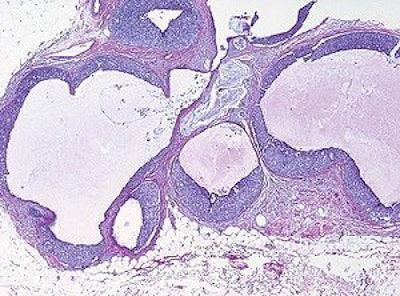

60-year-old woman with history of left mastectomy presents for follow-up MRI examination of right breast with normal mammogram and normal physical examination. Above, sagittal fat-suppressed image of right breast after contrast injection immediately before biopsy confirms presence of mass (arrow). Below, sagittal fat-suppressed image of right breast immediately after 9-gauge MRI-guided vacuum-assisted biopsy shows obturator (arrow) in high-signal hematoma obscuring biopsy site.